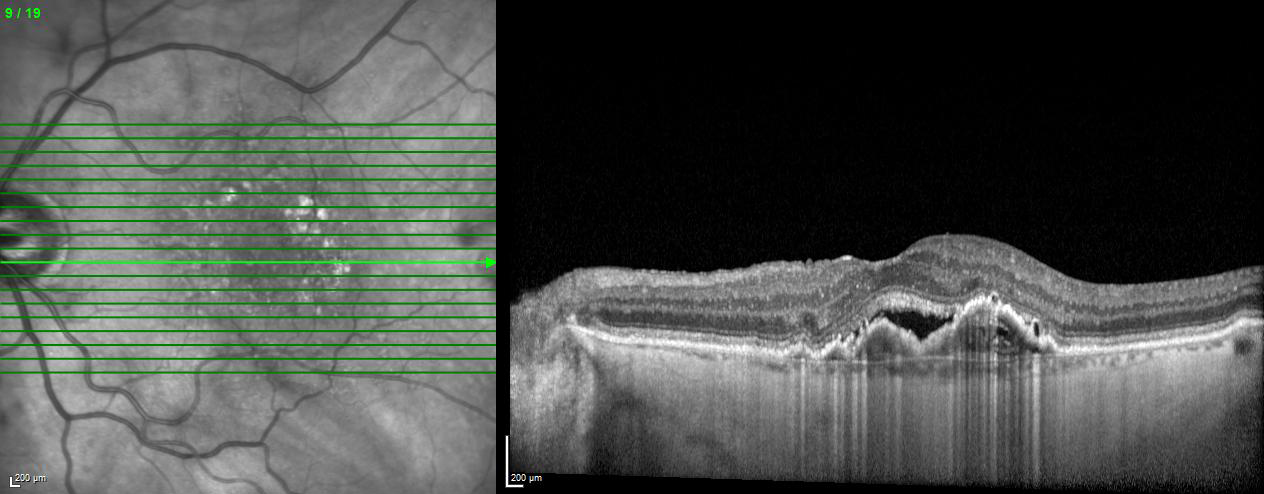

EDI – Enhanced Depth Imaging Mode

The Enhanced Depth Imaging Mode (EDI) of the SPECTRALIS is an OCT imaging technology that enables better visualization of choroidal vasculature. By automatically inverting the image and leveraging the benefits of technologies like TruTrack Active Eye Tracking and Noise Reduction, SPECTRALIS delivers superior images to depict the choroid, allowing to manually measure choroidal thickness.

Semi‐Automated Quantification of Retinal and Choroidal Biomarkers in Retinal Vascular Diseases: Agreement of Spectral‐Domain Optical Coherence Tomography with and without Enhanced Depth Imaging Mode